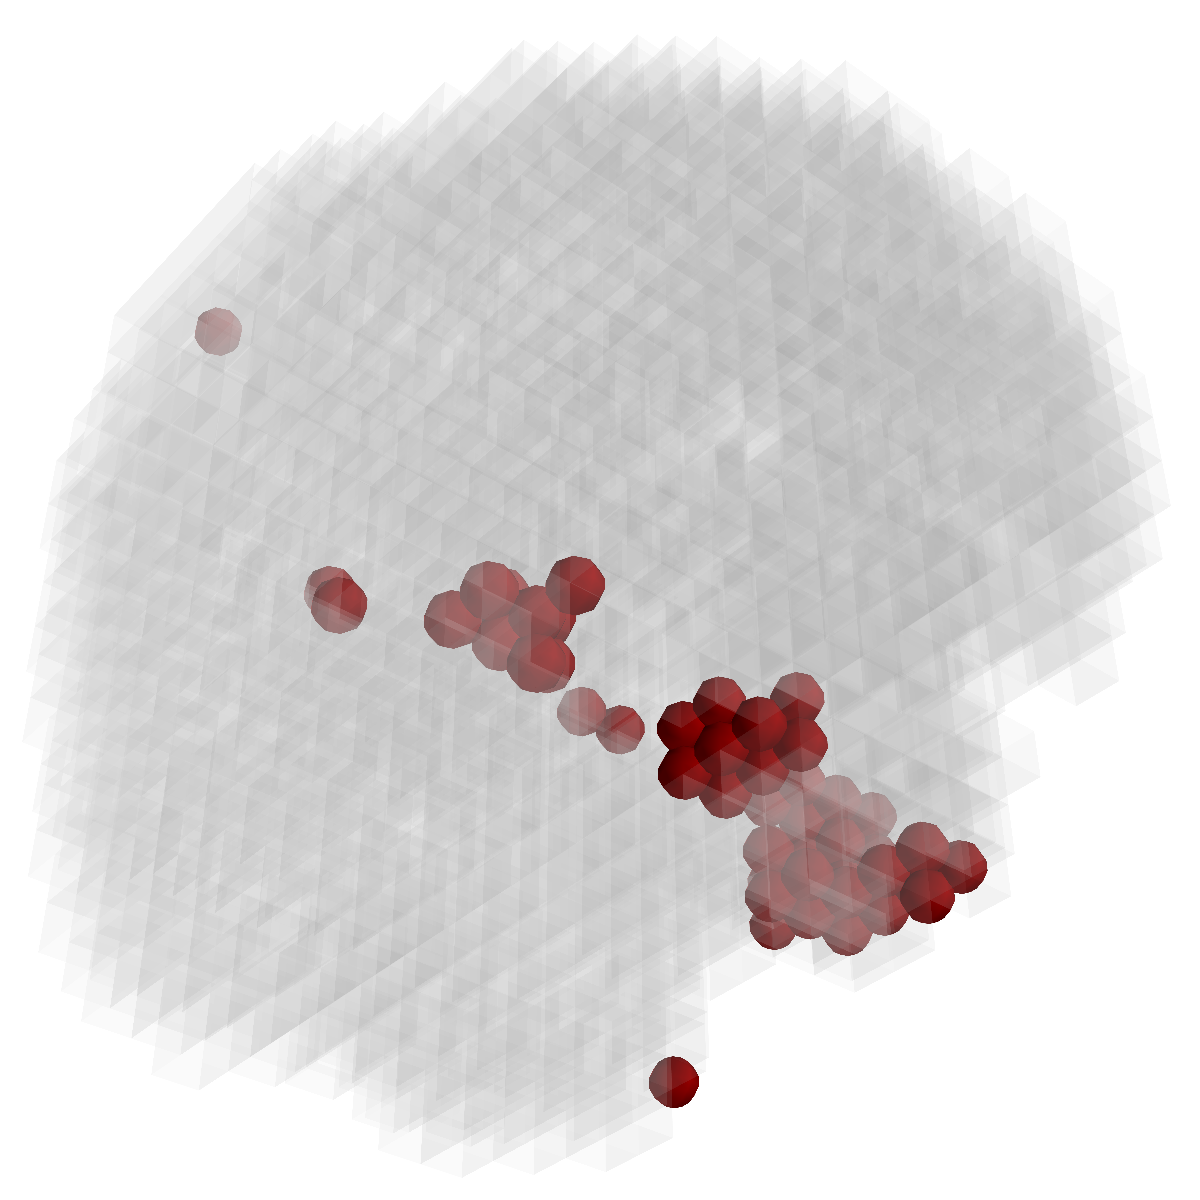

Figure 3: Stability of selected voxels across different folds of the cross-validation. The results of 5 different folds are shown in (a)-(e). The voxels with positive β𝛽\beta are in brown, negative ones are in blue. The common/overlapped voxels selected in all 10 folds are shown in green (f). The top row illustrates voxels selected by the lasso model, the mid row illustrates those of GFL and the bottom row shows those of n2superscript𝑛2n^{2}GFL.

Feature Stability. In Figure 3, we show the selected voxels across different folds of CV333Here, parameters were determined by accuracy. Similar results were observed using parameters producing same level of sparsity.. As shown, the selected voxels by lasso vary much across different folds, whereas the selected voxels by GFL are more stable. However, by assuming the positive correlation between the features and the disease labels in n2superscript𝑛2n^{2}GFL, we further increase the stability. To quantitatively evaluate the stability gain, we denote the variables of the k𝑘kth fold of CV as 𝜷(k)𝜷𝑘\boldsymbol{\beta}(k). We introduce two measurements here. In (?), the Estimation Stability (ES) is proposed to measure the stability of the estimation

where ##\# is the number of elements in a set. In Tab. 3, both measurements quantitatively suggest n2superscript𝑛2n^{2}GFL obtains much more stable voxels due to the consideration of the correlation between the features and the disease labels 444We notice that, in (?), the stability is computed using the top 50 positive voxels because these voxels are believe to be the most atrophied ones. By computing the stability of all non-zero voxels, the mDC of GFL drops around 30%percent3030\%. This clearly shows that the instability is caused largely by the undesirable voxels that disagree with the correlation prior (those scattered blue voxels in the mid row)..